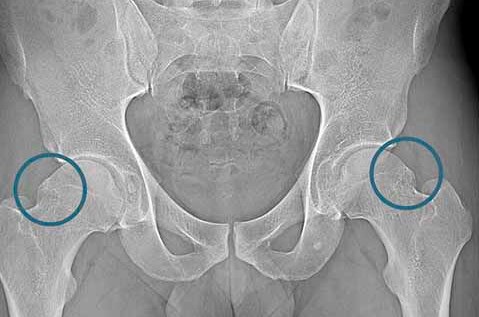

• Femoral Neck Fracture

Femoral Neck Fracture

A femoral neck fracture is one of the most common types of fractures involving the hip joint. In elderly individuals, it most often occurs as a result of a low-energy fall, frequently in the presence of osteoporosis, which significantly increases the risk of complications and mortality. Surgical treatment—depending on the type of fracture, the patient’s age, and functional status—includes either...